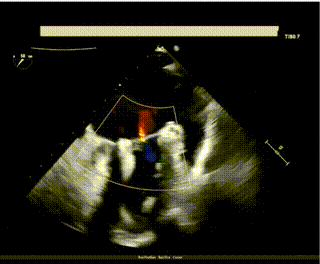

此次手术演示的患者是一名79岁老年女性,既往曾行永久起搏器置入术,合并高血压病、慢性肾脏病等,超声心动图提示“二尖瓣重度反流,A3区脱垂。外科手术高危,STS评分9.71%。

TEE外科视角见偏心反流

术前,王建安教授团队经过充分评估后选用DragonFly器械,术中在超声引导下建立右侧股静脉入路、精准穿刺房间隔,之后继续在经食道超声引导下将瓣膜夹器械输送到左心房,再利用多视角评估瓣膜夹位置和夹合效果。

超声评估少量反流,无残余脱垂,平均跨瓣压差2mmHg。经在场专家讨论后,决定释放二尖瓣瓣膜夹。

最终超声评估显示二尖瓣少量残余反流,二尖瓣平均跨瓣压差2mmHg。患者情况良好,手术顺利完成。